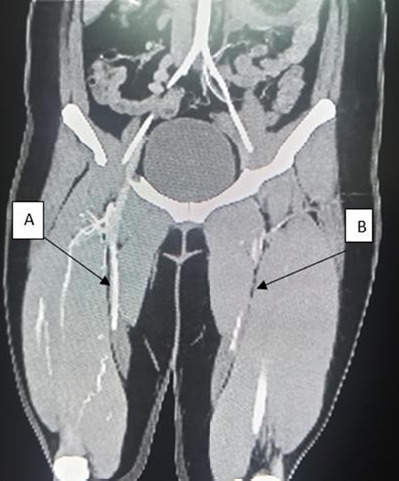

Ergotism is a rare but potentially serious condition characterised by peripheral vasospasm. Its diagnosis is challenging because the presentation varies depending on the type and location of the affected blood vessels. Ergot alkaloids, including ergotamine, are metabolised by the cytochrome P450 isoenzyme CYP3A4. Concurrent use of ergotamine with CYP3A4 inhibitors can significantly increase the risk of ergotism. However, this potentially dangerous drug interaction is often underestimated in general practice. Herein, we report the case of a middle- aged woman with a history of migraine headaches, who was treated with Cafergot (ergotamine tartrate and caffeine). After the initiation of human immunodeficiency virus therapy with Kaletra (lopinavir/ritonavir), she experienced recurrent episodes of bluish discoloration, livedo reticularis and tingling sensation in her upper and lower extremities over several years. Despite multiple hospital visits and extensive diagnostic workups, including normal blood investigations and biopsy, the correct diagnosis of ergotism-induced vasospasm due to ritonavir-ergotamine interaction was delayed. This diagnosis was supported by CT angiography, which demonstrated vasospasm of the femoral arteries. The patient's symptoms significantly resolved following ergotamine discontinuation. Ergotism is a self-limiting condition that can be fatal if not recognised and treated promptly. This case highlights the importance of awareness, particularly in primary care settings, on the potential drug interaction, principally in patients receiving drugs that inhibit CYP3A4, such as protease inhibitors. Clinicians should have a low threshold for suspecting ergotism in patients with recurrent or unexplained limb pain, numbness and skin changes, especially if they have a history of ergot alkaloid use.